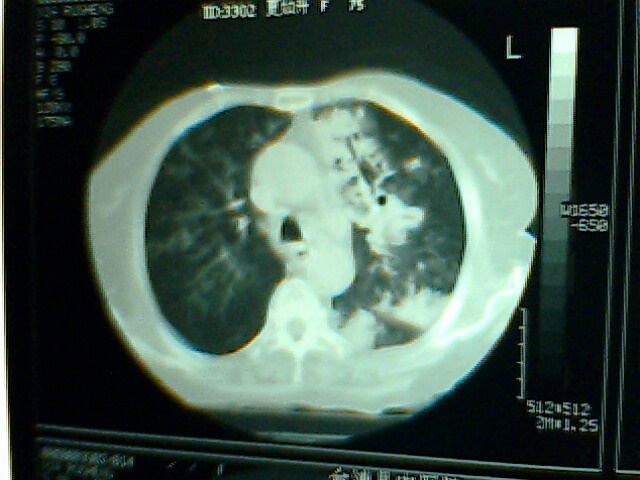

以下是引用hhx58在2009-9-11 19:48:00的发言:[br]有4个是心电监护的电极。[br]ct图片可见有肺气囊。但未拿到片上传。

以下是引用dyqct在2009-9-12 8:42:00的发言:[br]慢性支气管炎合并间质纤维化、肺气肿、支气管扩张、感染。建议ct进一步检查。

以下是引用黑白光影在2009-9-12 16:43:00的发言:[br]慢支并感染(霉菌?)